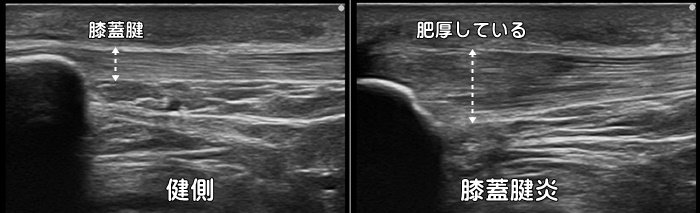

膝蓋腱炎・ジャンパー膝

膝蓋腱炎・膝蓋靭帯炎はバレーボールなどのジャンプ動作で発症するため別名ジャンパー膝とも呼ばれます。トレイルランナーが転倒し膝を強打した際にも好発します。重症化すると膝蓋骨や脛骨付着部の低エコー像(断裂)や腱の肥厚、また炎症による血管増生が見られます。